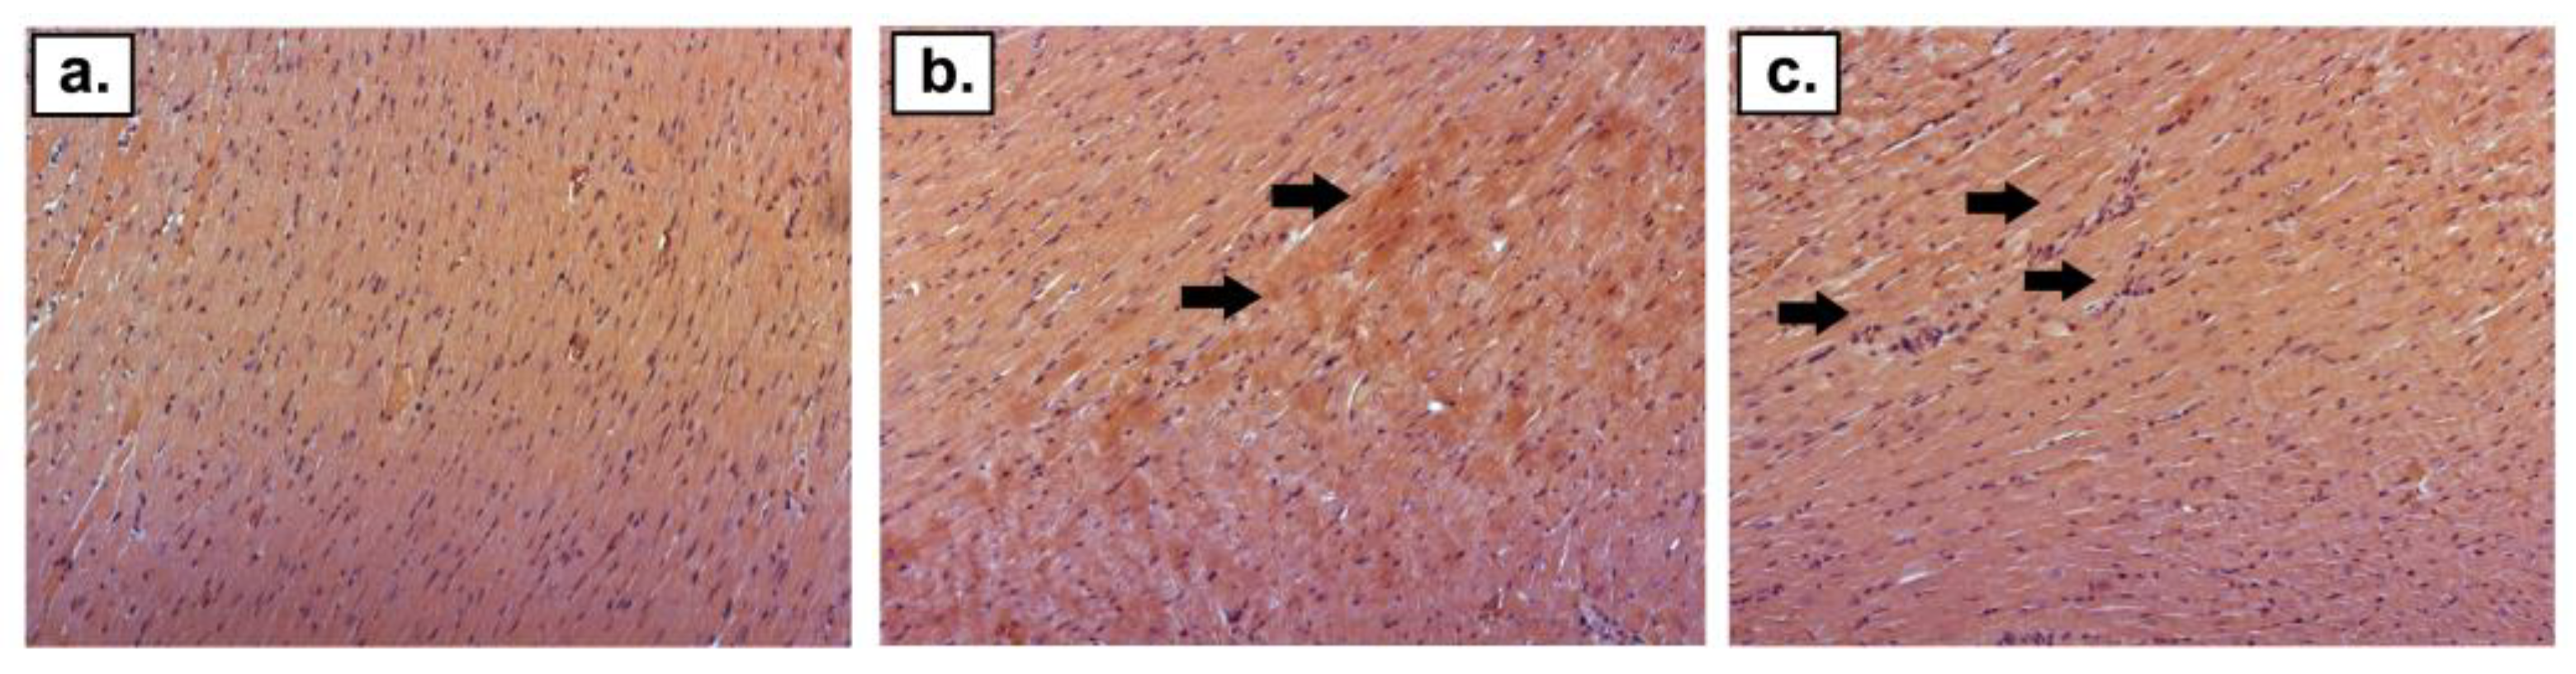

2.2. Histological Staining

| Morphological Feature | CTRI | CTRII | DOXI | DOXII | DOX + DEX + CVDI | DOX + DEX + CVDII | DOX + DEXI | DOX + DEXII | DOX + CVDI | DOX + CVDII |

|---|---|---|---|---|---|---|---|---|---|---|

| Mononuclear cell infiltration | − | − | + | ++ | + | ++ | − | − | + | ++ |

| Distribution of eosinophils | − | − | + | + | + | + | − | − | + | + |

| Collagen deposition | − | − | + | + | − | + | − | − | − | + |